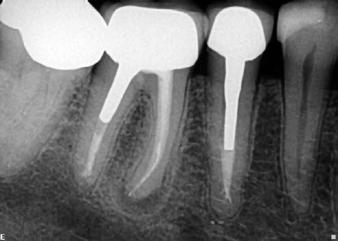

(2. ábra). A kiindulási vizsgálatot követően megkezdődött a páciens endodonciai ellátása (3. ábra). A jobb alsó kismetszőfogat (41) a beutaló orvos már előzetesen megtrepanálta (4. a. ábra), így csak a bal alsó fogban (31) kellett a hozzáférési nyílást kialakítani (4. b. ábra). A jobb alsó fogban lévő gyökércsatornát ISO #25 gyökércsúcsi átmérővel rendelkező 4%-os konicitású gyökérkezelő tűvel (25/.04), míg a bal alsó fogat egy mérettel kisebb (20/.04) eszközzel tágítottuk fel (VDW.ROTATE;VDW) (5. a–c. ábra). A gyökércsatorna átöblítése során lézeres aktiválást végeztünk Er,Cr:YSGG lézerkészülék (Biolase) segítségével (1,5 W, 100 Hz), majd a csatornákat előkészítettük a végleges gyökértömés befogadására. A jobb alsó fogban (41) CSBS sealert és egy poén technikát alkalmaztunk, míg a bal alsóban (31) dugattyú technikával készítettük el a gyökértömést (6. a–e. ábra). A gyökértömés behelyezését követően egyből kontrollröntgent készítettünk (7. ábra). A hat hónappal később készített kontrollfelvételen jól megfigyelhető volt a periapikális lézió gyógyulása (8. ábra)

1. ábra: Kiindulási röntgen. A felvételen jól látható a betört eszköz és a periapikális lézió.

2. ábra: Kiindulási CBCT-felvétel. A betört eszköz mélyen a gyökércsatorna görbülete mögött található.